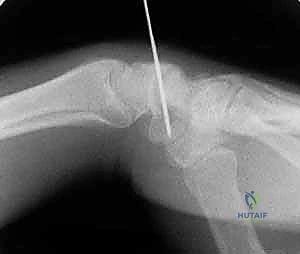

تقنية "التثبيت عن طريق الجلد" (Percutaneous Fixation) هي إجراء جراحي طفيف التوغل (Minimally Invasive). بدلاً من فتح الرسغ، يقوم الجراح بإجراء ثقب صغير جداً في الجلد (لا يتجاوز 3-5 مليمترات). من خلال هذا الثقب، وباستخدام جهاز الأشعة السينية المباشر في غرفة العمليات (C-arm Fluoroscopy)، يتم إدخال سلك توجيهي دقيق، ثم يتم إدخال مسمار خاص يسمى "مسمار ضغط بدون رأس" (Headless Compression Screw) مثل مسمار هيربرت (Herbert Screw).

الخطوة 2: تحديد مسار المسمار بدقة (Guidewire Placement)

هذه هي الخطوة الأكثر أهمية والتي تتطلب مهارة استثنائية. يقوم د. هطيف بعمل شق صغير جداً (بضعة مليمترات). باستخدام جهاز الأشعة، يقوم بإدخال سلك معدني